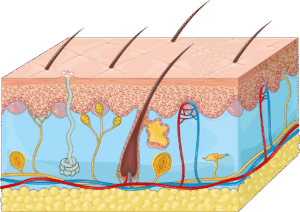

7. The Integumentary System (Skin)

Structure and functions of the skin

Skin layers (epidermis, dermis, subcutaneous)

Effects of massage on skin temperature and condition

Recognising skin conditions or contraindications